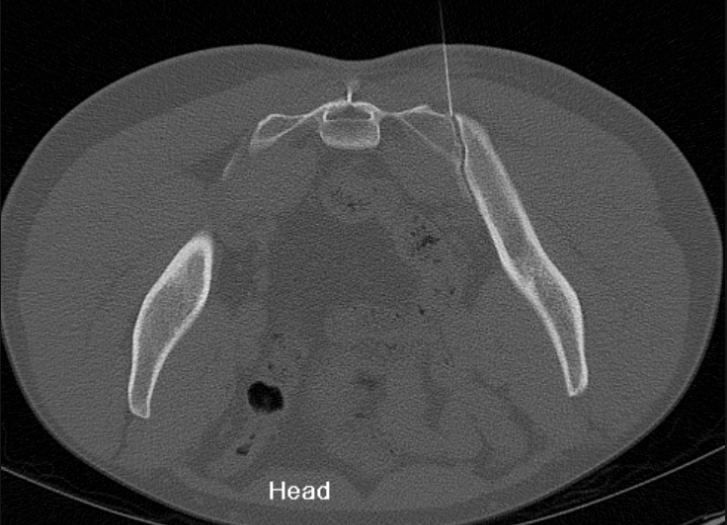

3. Sacroiliac joint injection (CT guided)